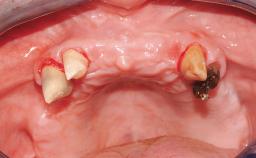

A healthy 31-year-old female patient presented with a failing maxillary left lateral incisor crown. The crown regularly loosened, and the remaining tooth was neither restorable nor rational to treat. The patient had a high smile line, a medium soft tissue biotype with a compromised mesial papilla (shorter than the contralateral one), and a horizontal scar in the buccal soft tissue as a result of past periapical surgery.

| Timing of placement | Immediate Placement (extraction sockets) (Type I) |

| Radicular morphology | Uniradicular |

| Available apical bone to achieve primary stability | Sufficient height ( ≥ 4 mm) and width (> 2 mm around apex of planned implant) |

| Socket walls | Intact |

| Thickness of buccal wall | less than 2 mm |

| Anticipated residual defect after implant placement | 2 mm or less |